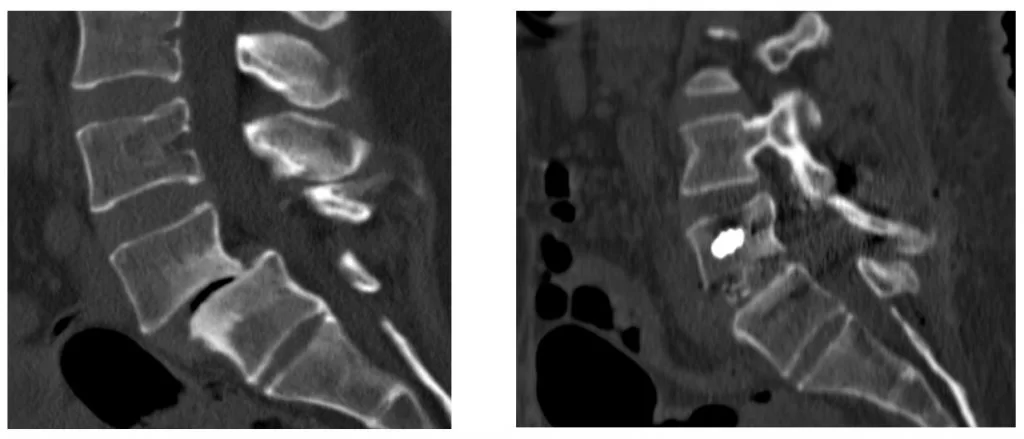

- Αστάθεια σπονδυλικής στήλης: Η σπονδυλική στήλη μπορεί να γίνει ασταθής εάν υπάρχει μη φυσιολογική ή υπερβολική κίνηση μεταξύ δύο σπονδύλων. Αυτή είναι μια κοινή επιπλοκή πχ.της σοβαρής αρθρίτιδας στη σπονδυλική στήλη. Η σπονδυλοδεσία μπορεί να χρησιμοποιηθεί για την αποκατάσταση της σταθερότητας της σπονδυλικής στήλης σε τέτοιες περιπτώσεις (Εικόνα 1 και 2).

Η προσπέλαση μπορεί να είναι πρόσθια (δηλαδή από μπροστά, όπως πχ. συχνά στον αυχένα, Εικόνα 2), οπίσθια (όπως πχ. συχνά στη μέση, Εικόνα 3) ή και πλάγια (όπως πχ. σε τεχνικές όπως το XLIF κλπ.)